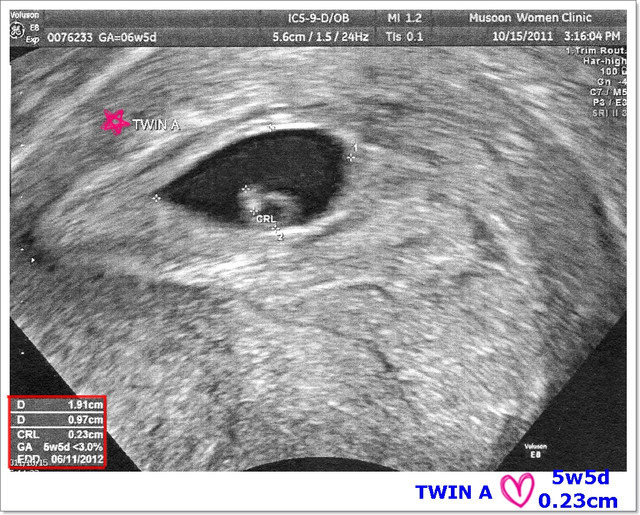

胚囊裡黑黑的就是羊水,白色的部份就是小BABY,

在左下角可以看到目前的週數是5W5D,

超音波師說機器會看胚囊的大小會自動計算出他的週數,

另外上面的CRL則表示是目前寶寶的大小,0.23公分。